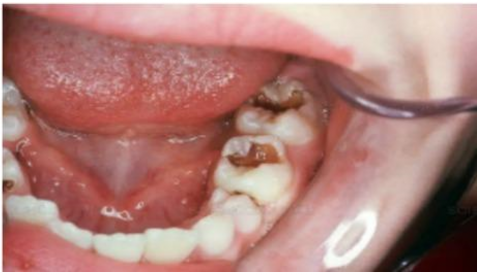

The dataset used in this study consists of 10,573 clinically sourced dental images, including contributions from publicly available repositories such as Kaggle. It provides a comprehensive foundation for training, validating, and testing the dental disease detection system [15]. The images are categorized into five distinct dental conditions: caries (2,382 images), gingivitis (2,349 images), hypodontia (1,251 images), mouth ulcers (2,541 images), and tooth discoloration (2,050 images) (Figure 1).

a

b

c

d

e

Figure 1. Dataset samples. (a) Caries, (b) Gingivitis, (c) Hypodontia, (d) Mouth ulcers, (e) Tooth discoloration

To facilitate the deep learning process, the dataset was partitioned into three subsets: 70% (7,399 images) for training, 15% (1,585 images) for validation, and 15% (1,589 images) for testing. Each subset was structured to maintain a balanced distribution of the categories to ensure fair training and evaluation [16].

The images, saved in JPEG format, were preprocessed to conform to an input shape of 224 × 224 pixels with three color channels (RGB). They represent clinical-grade dental photographs captured under varying angles and lighting conditions, enhancing the model's ability to generalize across diverse scenarios. This dataset serves as a robust resource for building a reliable and accurate system for automated dental disease detection.